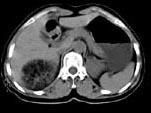

问题 女,53岁,右侧轻度腰背酸痛,行CT检查,如图所示,可能的诊断为 ( )

选项 A、右腹膜后脂肪瘤 B、右肾血管平滑肌脂肪瘤 C、右肾上腺腺瘤 D、右肾上腺嗜铬细胞瘤 E、右肾上腺髓样脂肪瘤

答案 E